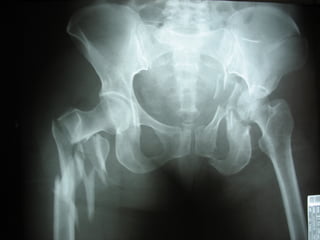

Fracture Pelvis

Associated injuries :

Head injury 51%

Extremity fracture 48%

Abdominal injury 28%

Peripheral nerve injury 26%

KUB injury 23%

Chest injury 22%

High mortality and morbidity rate

* 39% from hemorrhage

* 31% from associated injuries

* 30% from complications

Causes : traffic accident 84%

: falling from height 9%

: others 7%

Anatomy

Volume of Pelvis : ¶H( R² + 2Rr + r² )/3

R or r ↑ 2cm → vol. ↑ 1.3 litre

R or r ↑ 5cm → vol. ↑ 5.0 litre

Diagnosis

1. History of injury

* car accident

* motorcycle accident

* pedestrian accident

* falling from height

* crush injury

2. Physical examination

* marks at pelvis and perineum

* leg deformity or length discrepancy

* signs of ruptured urethra or bladder

* anorectal or vaginal lacerations

* pelvic compression test ???

3. Investigations

* pelvic film : AP , Inlet , Outlet , Judet

* FAST

* DPL

* CT scan

* Angiography